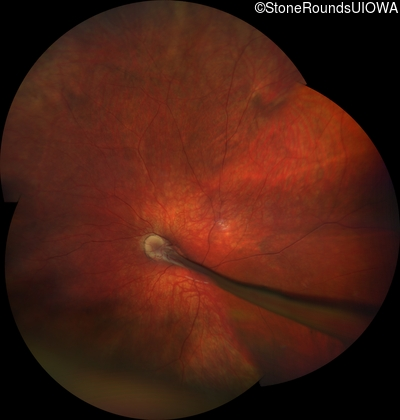

AD Familial Exudative Vitreoretinopathy (IIIE2b)

Age at visit: 23 months

This 23 month old male has had nystagmus since shortly after birth. He was born at term (7lbs 12oz).

AD Familial Exudative Vitreoretinopathy FZD4 Ser228Arg AGC>CGC   AD